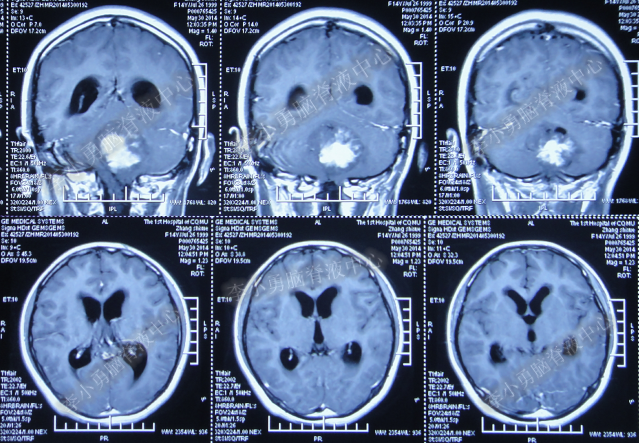

患者因恶心、呕吐伴头痛头晕,自行服药后无法自行缓解,于2014年5月29日就诊位于重庆的著名的三甲肿瘤医院,查全脑CTA和CT后诊断为“小脑蚓部占位伴幕上脑积水”(图-1、图-2)。

图-1:2014年5月29日全脑CTA

图-2:2014年5月29日头部CT